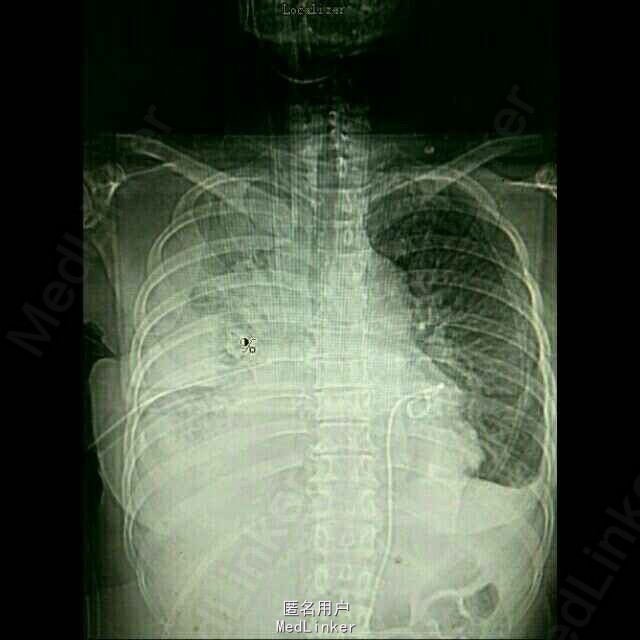

入院后予以胸水引流,复查ct,行心包穿刺引流,改善症状,加强营养,纠正低蛋白。情况稳定后,在全麻下行右侧胸腔持续热灌注化疗,术中胸腔镜见胸壁大量转移病灶,取部分组织送检EGFR。术后经密切观察治疗,度过热疗损伤急性期。症情平稳后出院。术后EGFR阴性。

术后一月复查胸部CT,右肺较前进一步好转,并行力比泰+顺铂化疗。目前继续后续治疗,计划力比泰长期维持。